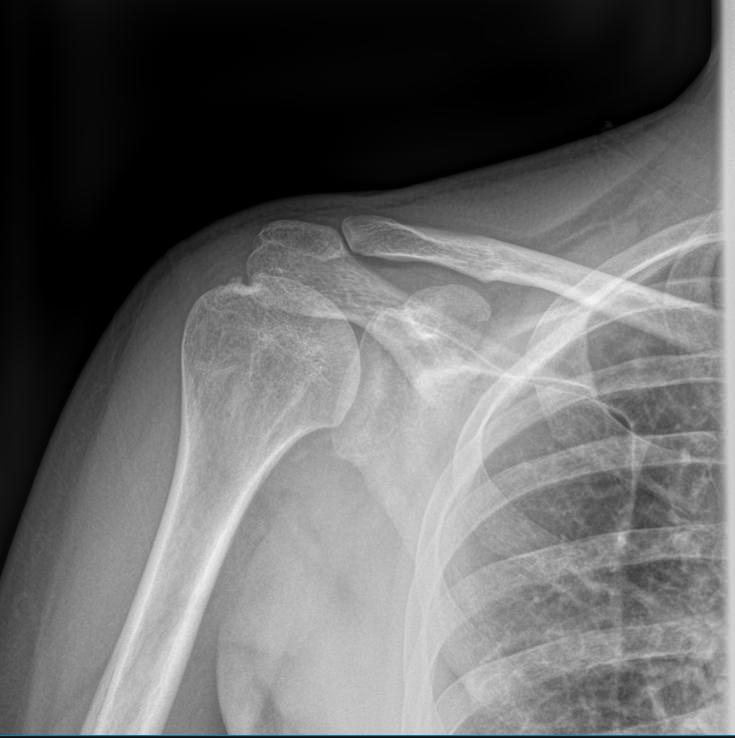

Плечевая кость ― одна из самых крепких в организме, что для ее повреждения требуется удар значительной силы. Переломы могут сопровождаться вывихами плечевого и локтевого суставов. Давно залеченная травма при неблагоприятных обстоятельствах может вызвать прерождение костной ткани.

Во всех случаях первичным методом диагностики будет рентгенография. Это простая и информативная процедура, которая не добавляет неприятных ощущений и быстро показывает полную картину патологии. Современное оборудование, которое используется в клинике «Доступная медицина», позволяет делать несколько снимков в течение короткого времени без опасности чрезмерного облучения.

Что покажет рентген плечевой кости

• Травматические повреждения, в том числе зажившие;

• Формирование костной мозоли;

• Патологические изменения костной ткани: разрежение, некроз, деструкция и другие;

• Состояние смежных суставов, вошедших в снимок;

• Опухоли и метастазы.